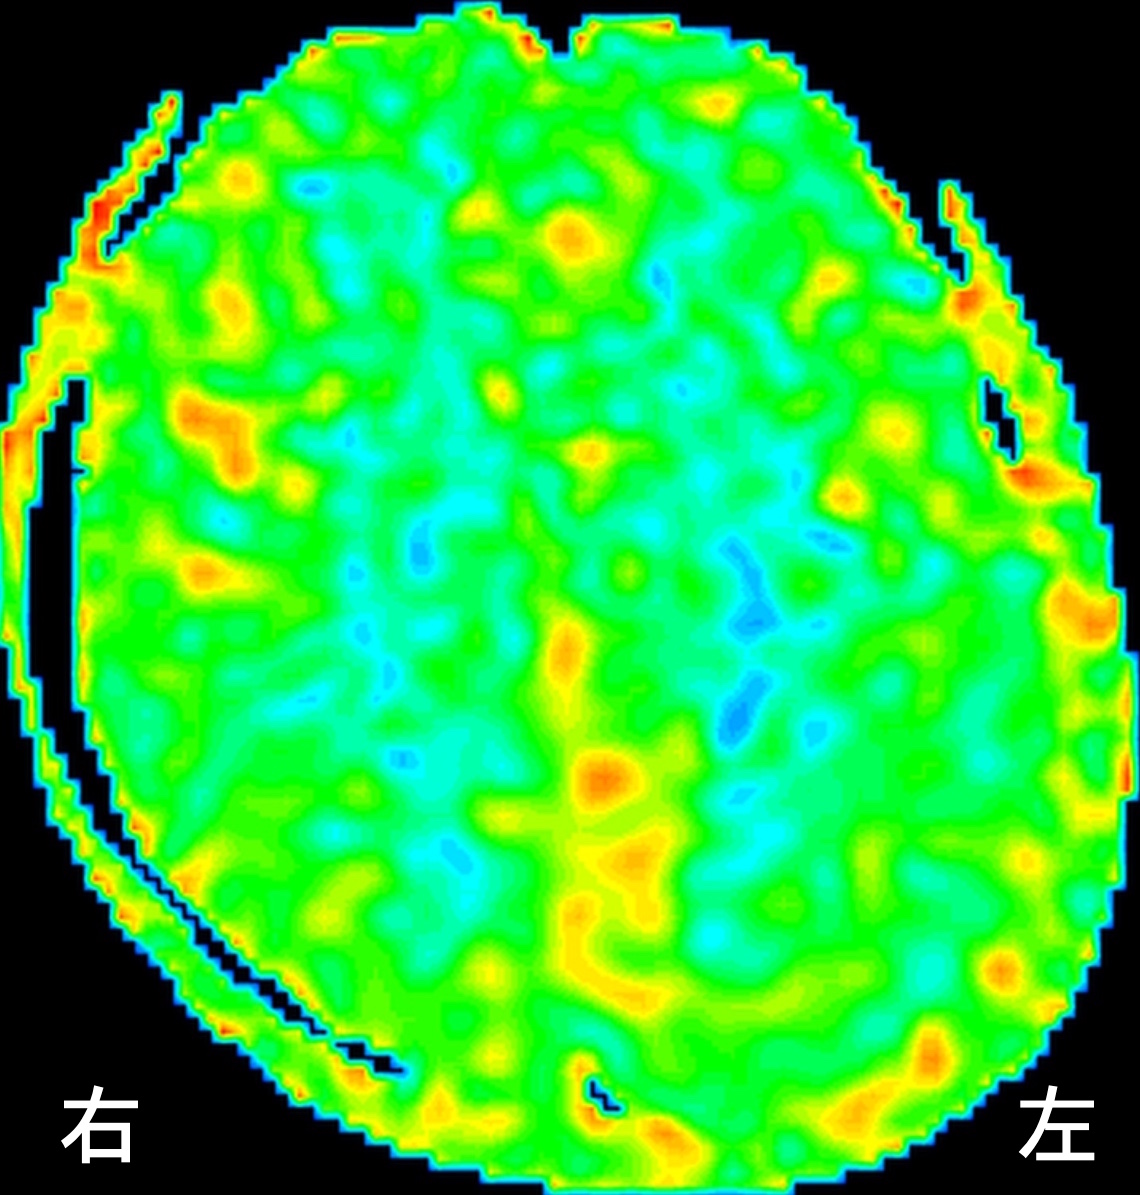

ASL(arterial spin labeling)法という、MRIで脳血流を評価する検査を行ったところ、

ASL早期

右の前頭葉、側頭葉、後頭葉で血流が低下しています。(青い場所が血流の悪い部分です)時間経過を追って血流の変化を見てみると、